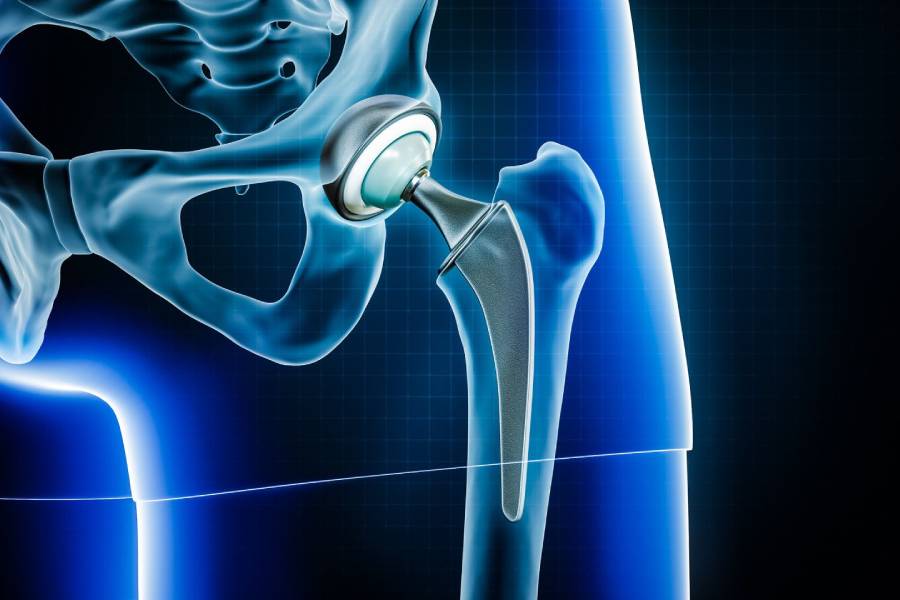

In a joint replacement hip surgery, the ball-and-socket structure of the hip joint is replaced with an artificial implant, helping patients regain pain-free movement after arthritis or hip fractures.

In Total Joint Replacement Surgery, the entire joint surface is replaced with an artificial implant. It's commonly performed for severe arthritis or trauma involving the hip, knee, or shoulder.